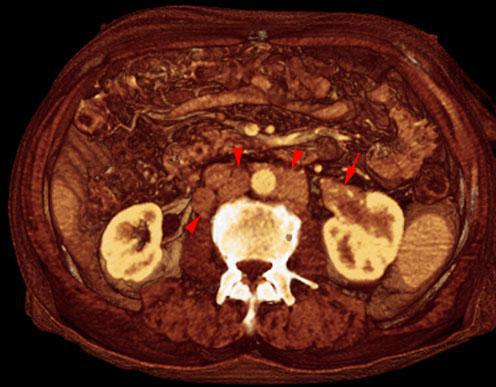

Metástasis renal de carcinoma broncopulmonar